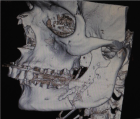

Sagittal split osteotomy (SSO) of the mandible is still an important part of orthognathic surgery, but “bad split” fractures that happen during the surgery are still a big problem. This report describes a rare case of bilateral bad split associated with highly compact mandibular bone (D1–D2 type) in a 53-year-old male undergoing mandibular advancement. The bone was too hard for the piezoelectric and rotary tools to work, and there was very little bleeding. This caused fractures in the cortex and lingual. Postoperative computed tomography confirmed the presence of highly dense bone, correlated with delayed healing and recurrence. Consistent pre-surgical CT scanning for an assessment of the density of the mandibular bone can provide essential information about the potential risk of the osteotomy procedure in the patient. Performing a careful bone quality and density examination pre-operatively will allow the surgeons to select the most appropriate instruments and surgical techniques that will fit the patient’s individual anatomy. Such a point escalates to being very significant when dealing with the geriatric population, as bone density increase can not only alter the fracture behavior but also the recovery process during and after surgery. The inclusion of regular CT-based bone density evaluations into the preoperative routine not only facilitates the anticipation of surgical difficulties but also results in safer and more efficient osteotomies.

Figure 2

Figure 1